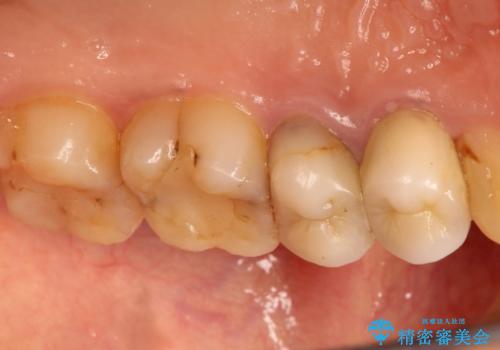

かぶせ物と詰めてある修復物を除去すると歯肉の中まで虫歯になっていました。

歯を部分矯正で引き上げて、虫歯を徹底的に取り除き、適合の良いかぶせ物を装着する計画としました。

深い虫歯の治療は、治療が長期化したり、困難になることがあります。

虫歯にならないことも大事ですが、治療した歯の再治療が必要ないように、精密な治療をすることもとても重要です。